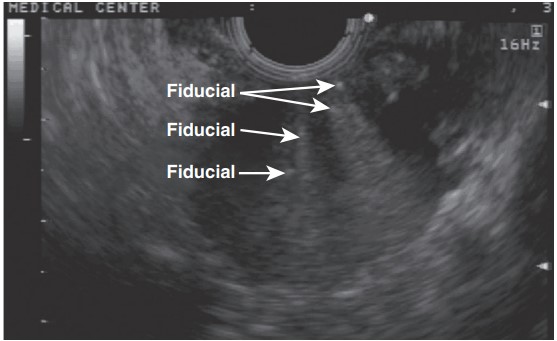

Although many EUS-based techniques primarily target the ablation or control of pancreatic malignancies, they also play a vital role in enhancing the delivery of radiation therapy. This is achieved through the placement of radiopaque markers directly into the tumor, facilitating targeted treatment and potentially improving outcomes for patients with various types of cancers.